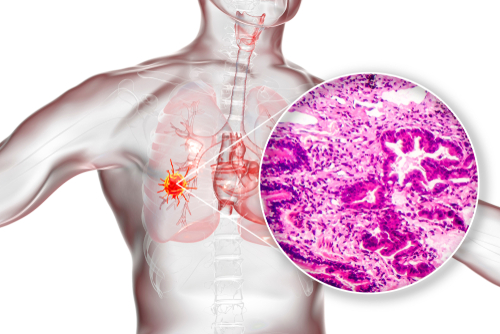

Limited resection may be a surgical treatment option for patients who have stage IA adenocarcinoma with spread through air spaces (STAS). However, lobectomy may be the best choice for patients with larger tumors, such as stage IB disease, according to recent study findings.

Kuan Xu, MD, and colleagues retrospectively analyzed clinicopathologic features of 1566 patients with stage I adenocarcinoma in China from 2017 to 2020. Then they classified the patients according to STAS status and surgical method to evaluate if limited resection predicted poorer survival.